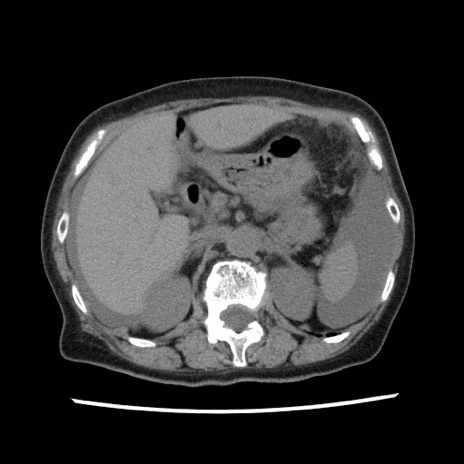

症例1(横断像)

【症例】80歳代女性

【主訴】腹痛

【現病歴】8時間前から腹痛あり来院。

【既往歴】糖尿病、脂質異常症、子宮体癌にて子宮全摘術

【身体所見】意識清明・会話良好だが腹痛で苦悶様、全腹部にわたって反跳痛と圧痛あり

【データ】WBC 13600、CRP 0.14、LDH 224、CK 90